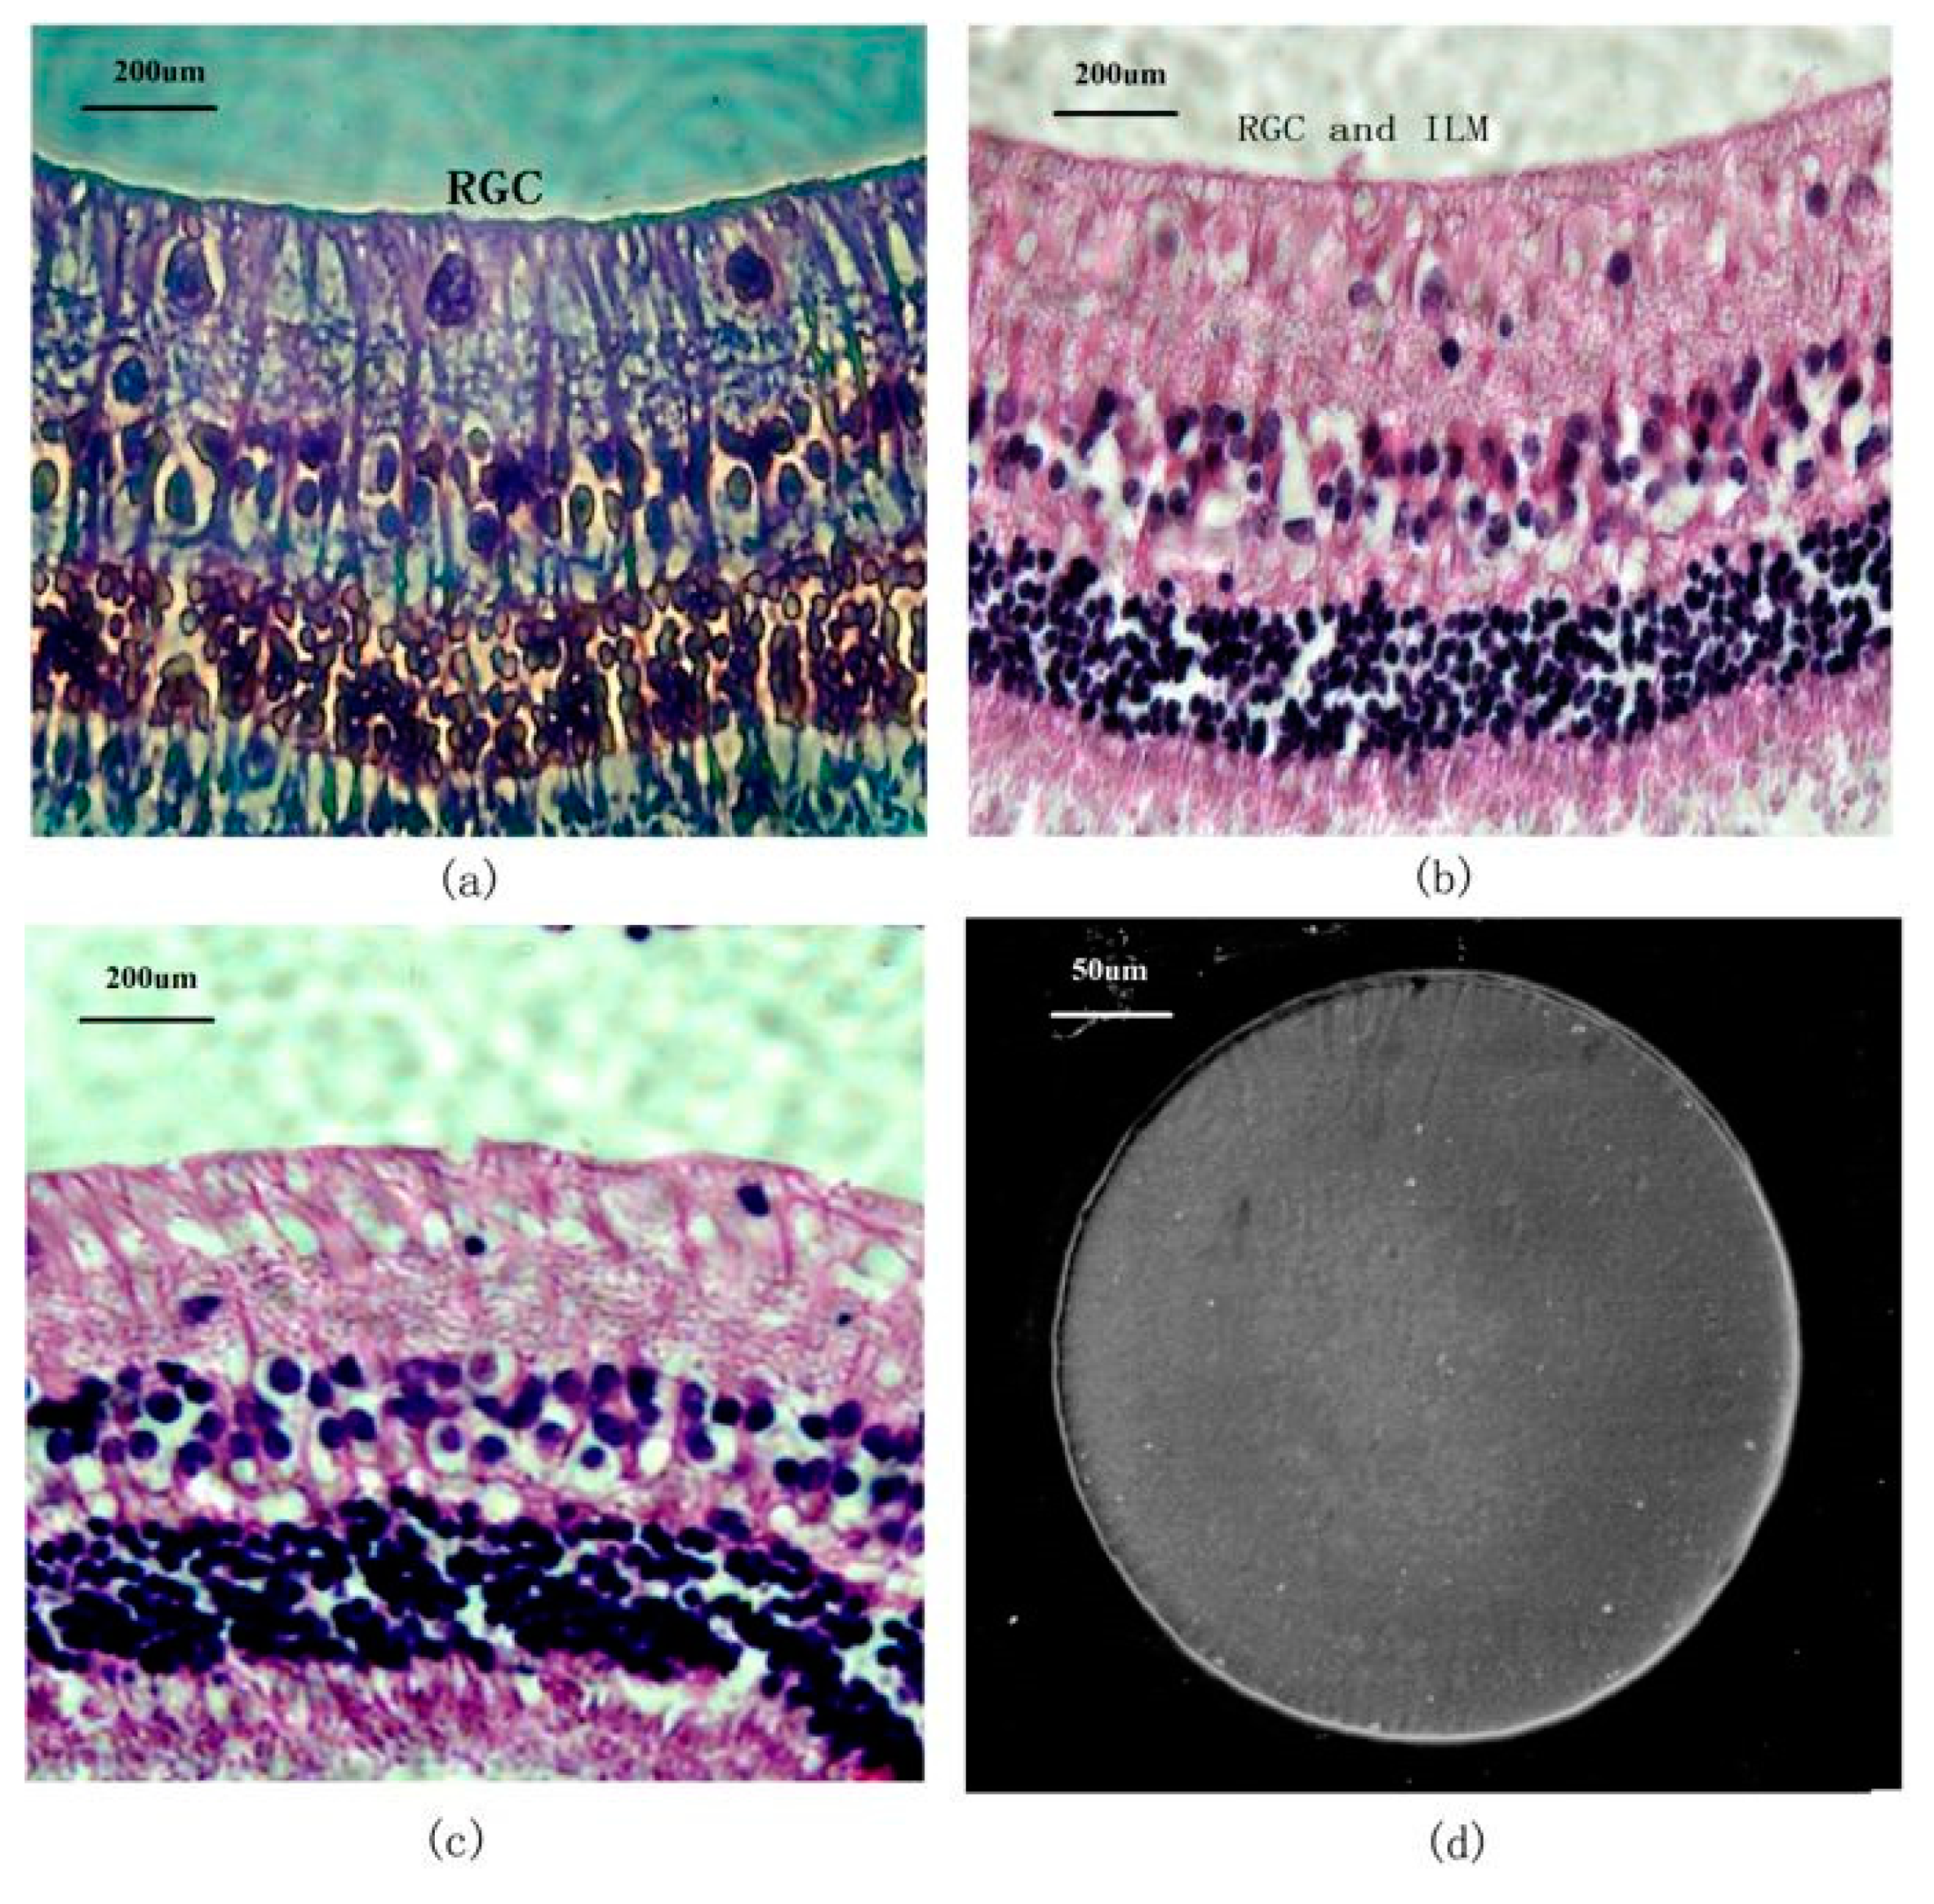

As a complement of the former, the second example of successful PI implantation is related to a commercial psPI (Durimide 7510) used in the preparation of MEMS for epiretinal electrical stimulation. Its reliability and stability were assessed by chronic 6-month implantation in rabbit eyes, which showed a nonirritant, biologically safe PI-based device with high biocompatibility and no mechanical pressure or mismatch. The study details the lack of cytotoxicity of the thin PI sheet, which did not bring any injury or modifications to the inner retina or its layers, as it can be observed in Figure 13a–c. Moreover, the PI material was immune to sterilization and the harsh biological environment, and, also important, no delamination was noticed 6 months after the implantation (Figure 13d) [41].

Figure 13.

Long term in vivo biocompatibility evaluation of a microelectrode array based on photosensitive Durimide 7510 polyimide layer implanted within a rabbit eye: (a) phase-contrast image (400×) of the inner retinal morphology at 6 weeks post-implantation (RGC: retinal ganglion cell layer; ILM: inner limiting membrane); (b) light microscope image (400×) of the inner retinal morphology at 6 months post-implantation; (c) light microscope image (400×) of the control rabbit retina; (d) SEM micrograph of the undamaged implanted electrode at 6 months post-operation. Reproduced from [41], with permission from © 2013 BioMed Central, under CC BY 2.0.